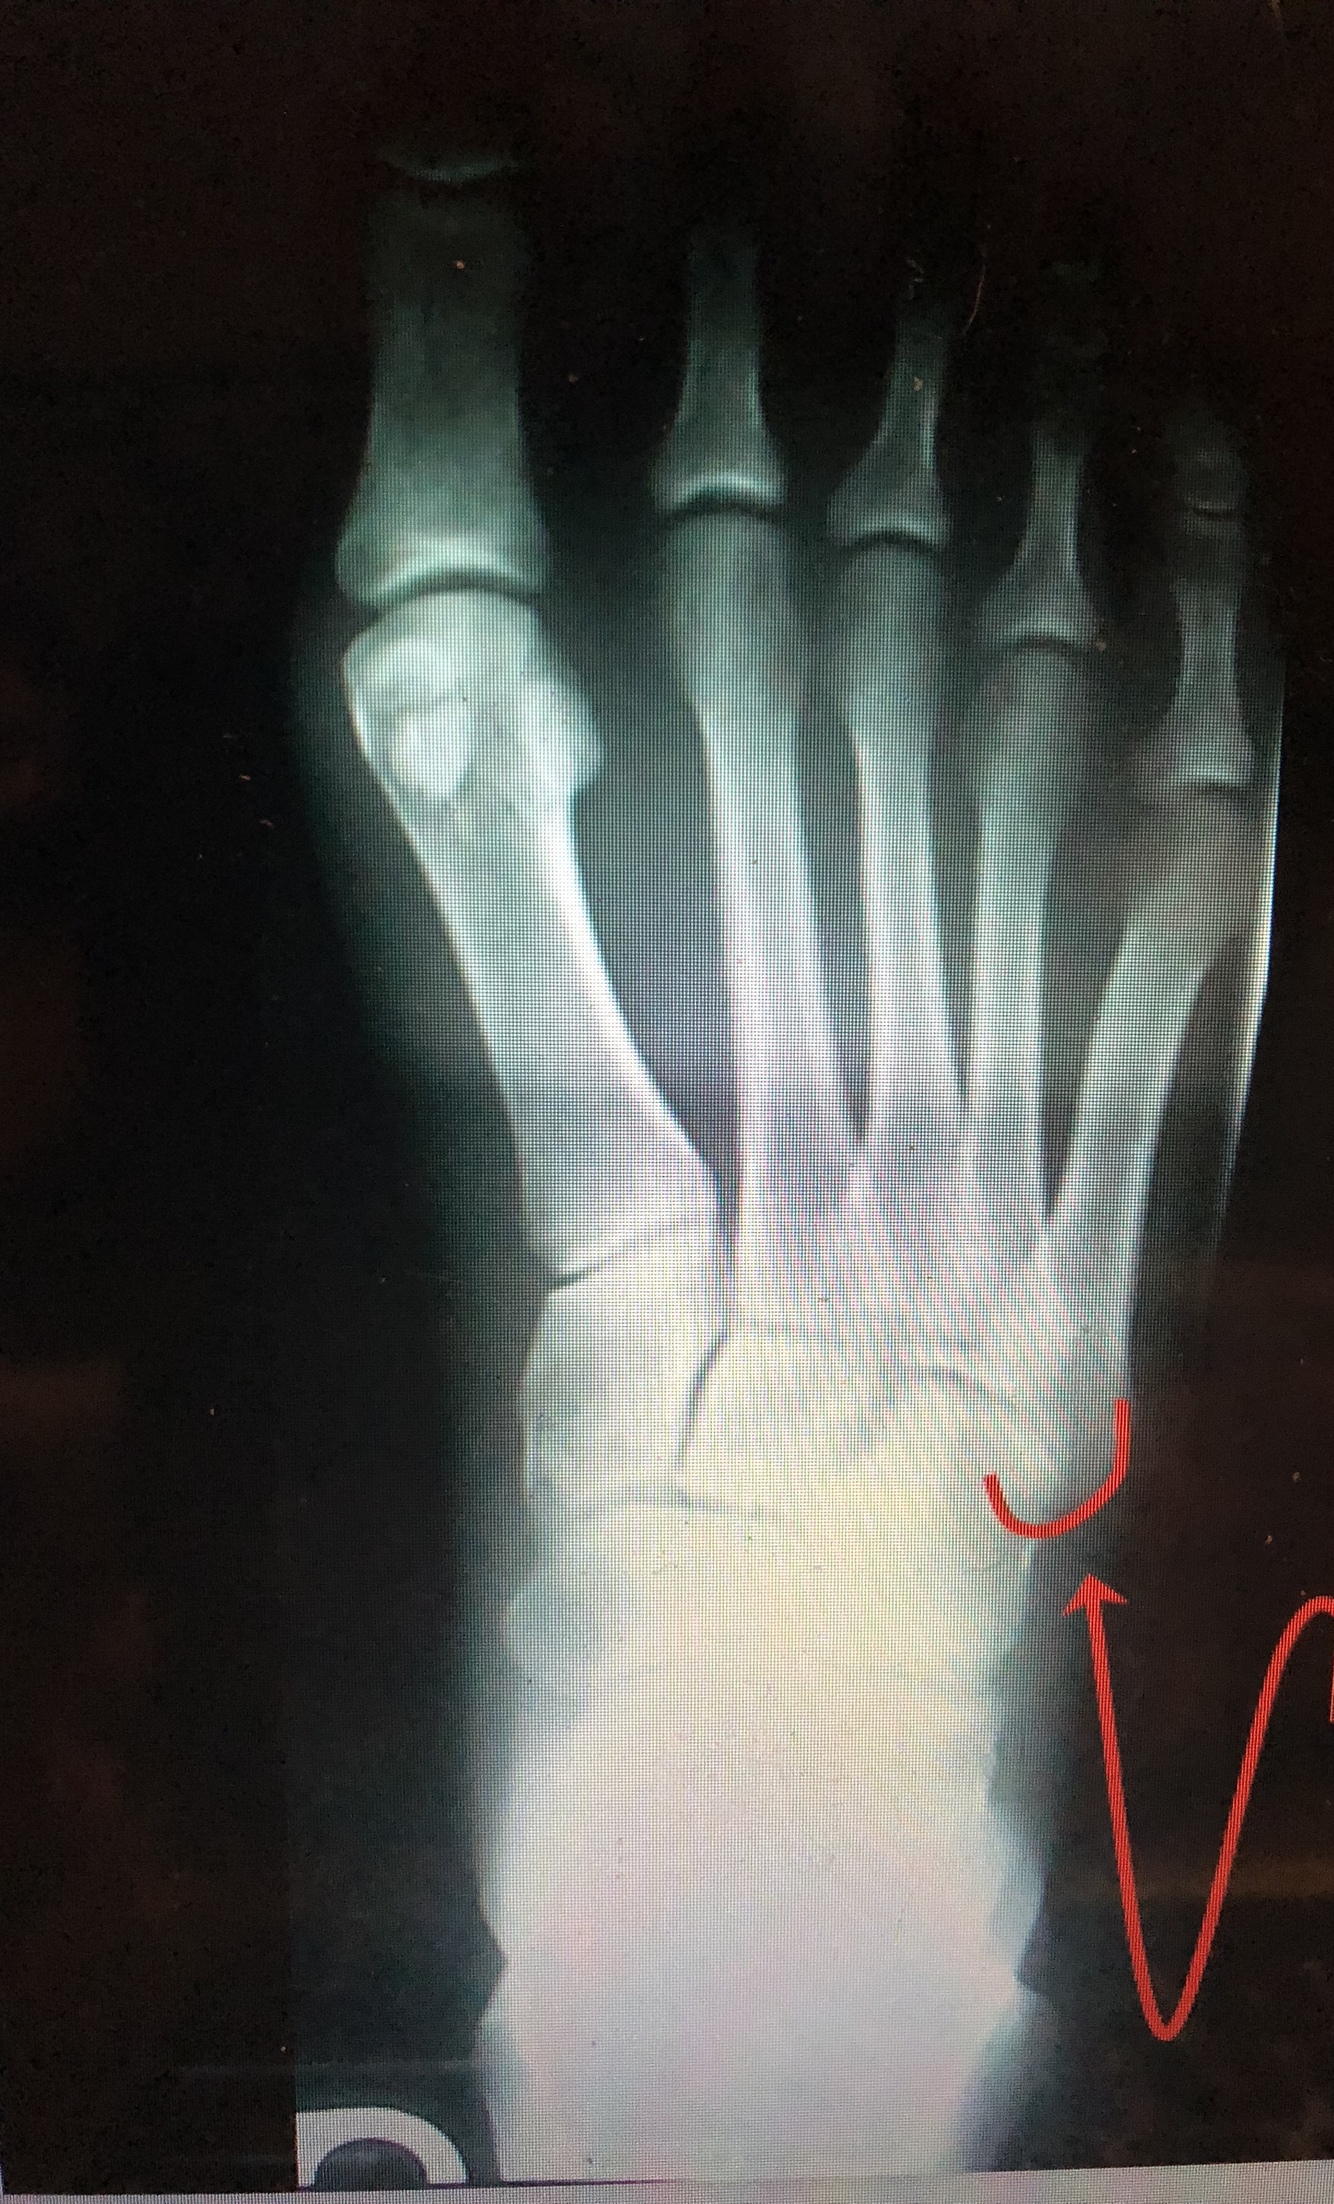

What is the red line?

head of 1st metatarsal

What is the dark blue line?

Neck of 2nd metatarsal

What is the yellow line?

Shaft of 3rd metatarsal

What is the light blue line?

base of the 3rd metatarsal

Styloid Process of the 5th Metatarsal

• Common fracture site in an inversion ankle sprain due to the pull of the peroneus brevis muscle